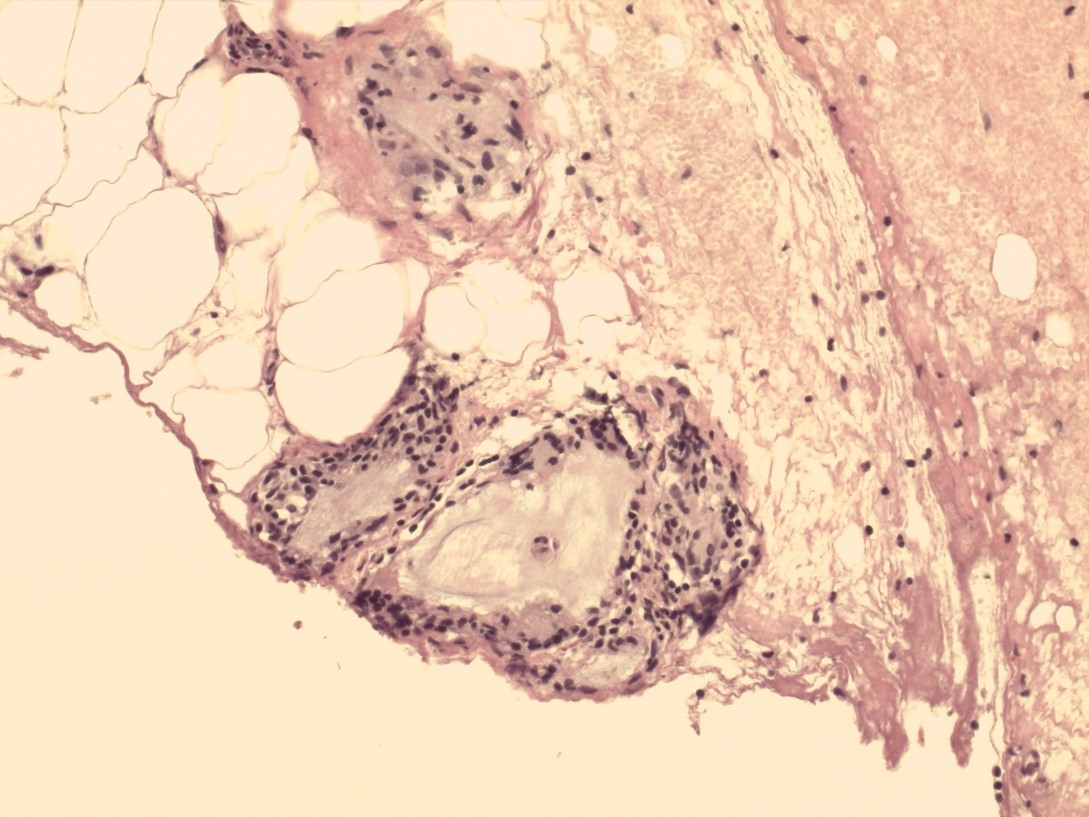

В фиброзной капсуле были заметны скопления крупных макрофагов с пенистой поверхностью. По сути, это клетки, фагоцитирующие гель, который далее остается в клеточной цитоплазме в виде вакуолей. Вблизи капсулы отмечалось неглубокое прорастание в гель тонких тяжей, состоящих из макрофагов, фибробластов и незрелых коллагеновых волокон. Последние разделяли ПААГ в прикапсулярной зоне на фрагменты. В одних из них гелевый материал сохранял свою гомогенность, в других приобретал мелкоячеистость, фибриллярную структуру. У пациенток с ПАМС местами определялись участки прорыва ПААГ в грудные мышцы с образованием гелевых «озер».

В подавляющем большинстве наблюдений поздних осложнений «гелевой» болезни (6 пациенток) гистограмма расценена как хроническое продуктивное воспаление различной степени выраженности, несмотря на клиническую картину острого воспалительного поражения. Оно проявлялось присутствием эпителиоидных и гигантских многоядерных клеток инородных тел с овальными гиперхромными ядрами, лимфоцитов и плазматических клеток практически по всей зоне гелевой аугментации (рис. 4). Самое большое количество гигантских клеток визуализировали в паренхиме МЖ на границе с гелем. Встречались даже единичные клетки Пирогова–Лангханса, характеризующиеся периферическим расположением овальных ядер. Наличие микроабсцессов в 2 наблюдениях говорило о деструкции соединительной ткани, обусловленной в том числе токсическим влиянием ПААГ. Как в первичном очаге, так и в зонах миграции обнаруживали гелеомы в виде межклеточных скоплений ПААГ, окруженные плотной капсулой из коллагена, фибробластов и гигантских многоядерных клеток. Размеры данных образований могли существенно отличаться друг от друга даже в пределах одной зоны (рис. 5). Железистая ткань МЖ в отдаленном периоде после порочной пластической операции у 100% больных была с выраженным склерозом, дистрофией и атрофией долькового аппарата; очевидно замещение последнего клетками жировой ткани. Следует отметить, что при длительном сроке залегания геля инволютивные изменения железистого аппарата (фиброз и облитерация паренхимы) у лиц старше 50 лет носили более выраженный характер, чем ожидаемые в данной возрастной категории.

Рис. 4. Биоптат ткани молочной железы: гигантские клетки инородных тел. Окраска гематоксилином и эозином (×400).

Рис. 5. Множественные гелеомы. Окраска гематоксилином и эозином (×200).